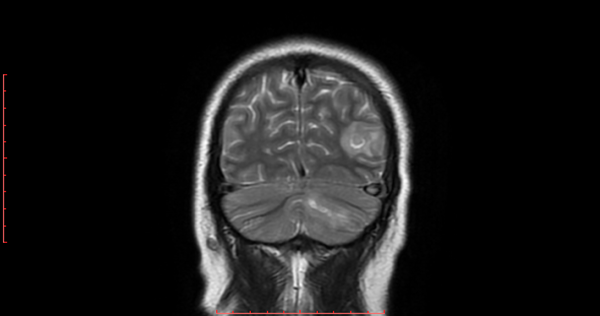

h. 3) Resonancia magnética cerebral corte coronal en secuencia T2. Se encontró zona focal heterogénea de predominio hiperintensa sin efecto de masa en lóbulo parietal izquierdo. En el hemisferio cerebeloso se observó imagen de forma lineal hiperintensa con edema perilesional. (Figura 3).

Figura 3. Resonancia magnética cerebral corte coronal en secuencia T2.